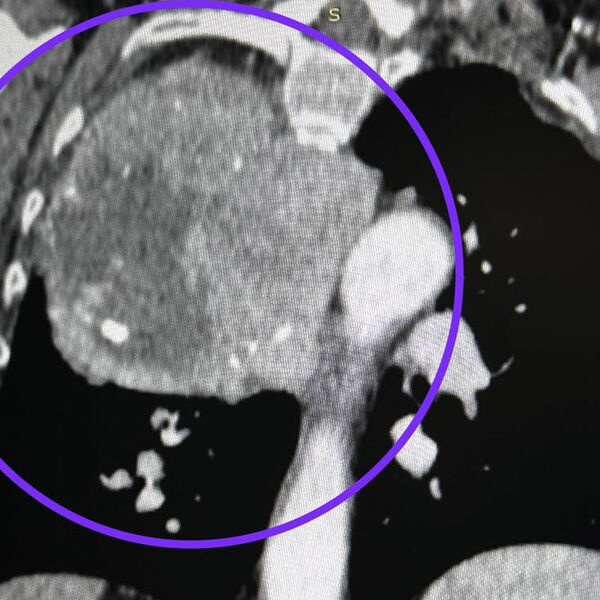

Пожилая россиянка мучилась кашлем и удушьем из-за опухоли, занимавшей треть грудной клетки

В Казани женщине удалили гигантскую опухоль, занимавшую треть грудной клетки

В Казани врачи Республиканской клинической больницы удалили у пожилой пациентки опухоль, которая занимала треть грудной клетки. О необычном случае медики рассказали в Telegram-канале медицинского учреждения.

По словам медиков, 75-летняя женщина почувствовала недомогание в декабре 2023 года: ее беспокоили постоянные боли в груди, ей стало трудно глотать пищу, появился странный кашель. Диагностика показала, что в груди у пациентки гигантская опухоль, выросшая из нижнего полюса щитовидной железы.

В 2024 году торакальные хирурги повторили вмешательство — они удалили опухоль через разрез между ребер за три часа.